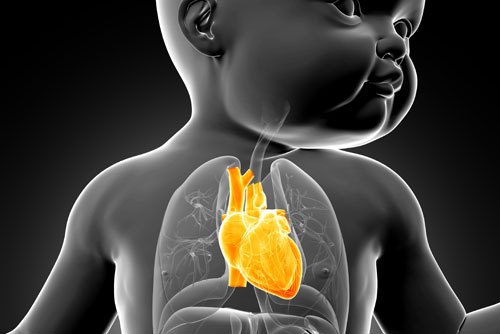

3 - Bebekte Gelişebilecek Kalp Hastalıkları

Gebeliğin 20. haftası, bebeğin kalp gelişiminde önemli bir yer teşkil eder. Uzmanlar hamileliğin 19-22. haftaları bebekte kalp için en ideal fetal anomali tarama zamanı olduğunu belirtirler. Anne karnındaki bebekte kalp ritim bozukluğu nedenleri ile bebekte kardiyak anomali için risk taşıyan genetik ya da çevresel pek çok faktörün bulunduğunu belirten uzmanlar, anne adayının diyabet hastası olmasından gebelikte riskli ilaç kullanmasına kadar birçok nedenin buna yol açabileceğini belirtiyorlar. En sık rastlanan kalp anomalileri arasında; fallot tetrolojisi (mor bebek hastalığı), büyük damar transpozisyonu, büyük kalp delikleri, ana damarlarda terslik ya da ağır darlıklara bağlı olarak kalbin bir tarafının gelişmemesi yer alıyor. Günümüzde birçok kardiyak anomali, gebelikte bu yolla tespit edilebiliyor.